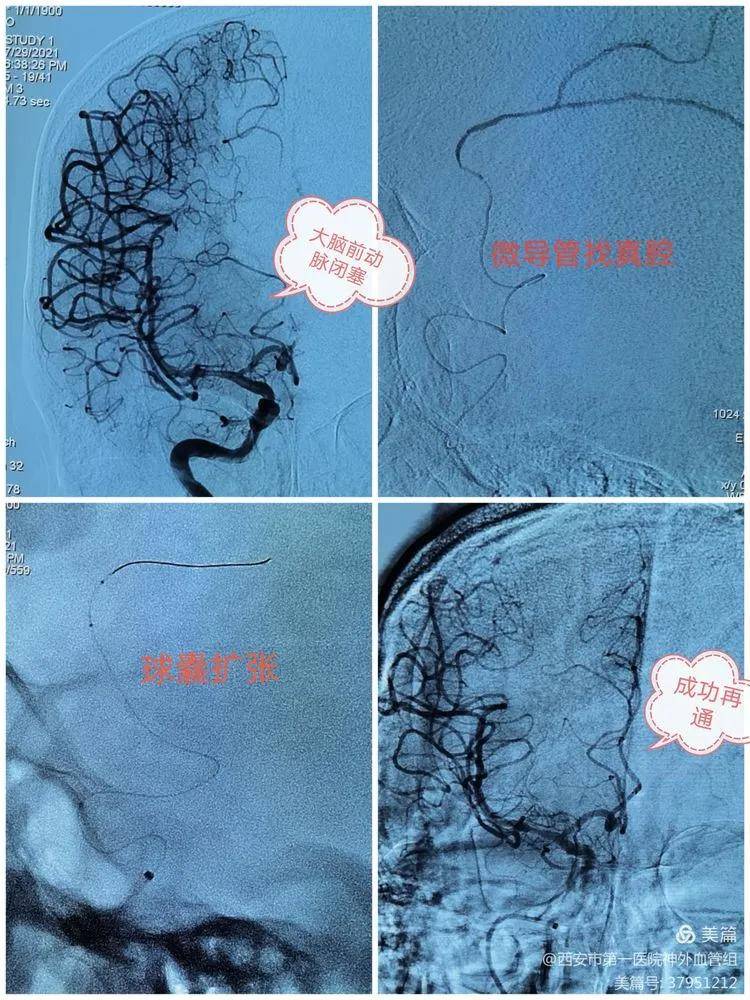

文章图片

我们不仅能修“大路” , 开通崎岖“小路”也胜券在握 。 68岁大爷 , 突发偏瘫及大小便失禁来院 , 核磁提示大脑前闭塞 , 大脑前供血区散发梗死灶 , 我们迎难而上 , 毫不畏惧 , 以行业领先的水准安全打通中枢要道 。 次日 , 患者症状逐渐好转!